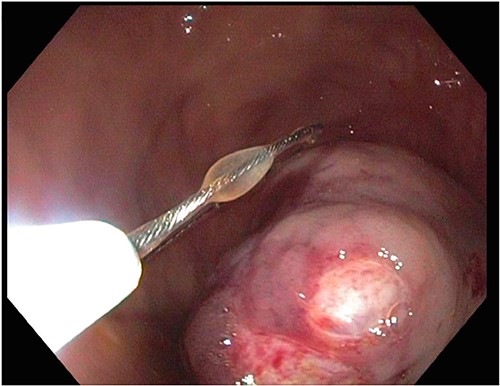

A 72-year-old patient with no past surgical history and a past medical history of developmental delay, hypertension and hyperlipidemia presented to the Emergency Department in mild distress with periumbilical abdominal pain, nausea and intractable vomiting for 1 day. The patient denied any hematemesis, bowel changes, fever, melena or hematochezia. On physical exam, the abdomen was unremarkable, and a computed tomography (CT) scan with contrast of abdomen and pelvis revealed a 5.6 × 5.3 cm heterogeneous mass arising from the body of the stomach extending into pylorus with no evidence of bowel obstruction and liver metastasis (Fig. 1). Subsequently, esophagogastroduodenoscopy (EGD) showed a large, fungating and ulcerated mass and it was reported to involve two-thirds of the luminal circumference in the gastric body (Fig. 2). Cold forceps biopsy showed gastric mucosa with hyperplastic changes, mild chronic active antral gastritis with focal intestinal metaplasia, negative for Helicobacter Pylori and dysplasia. Surgical management was discussed with the family, but they refused any surgical intervention.

A large fungating gastric mass arising from the body of the stomach on endoscopy.